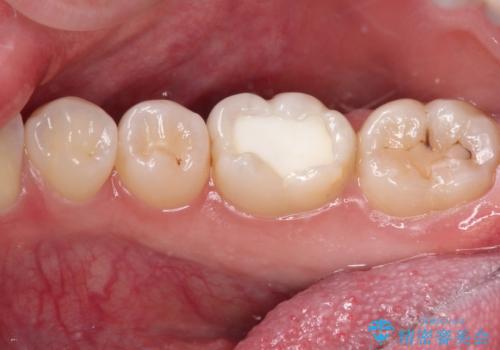

見た目、噛み合わせともに満足していただけました。

ラバーダム防湿を行い、セラミックの接着をすることで、唾液や血液などの接着阻害因子を排除することができます。